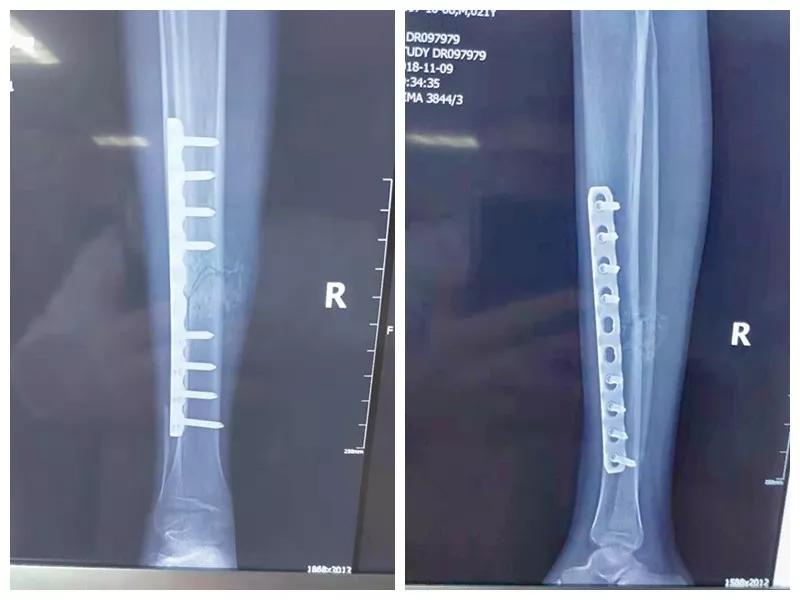

骨二科张延平主任接诊后经仔细询问病史,详细阅读近期X线、CT等病历资料,认为患者骨折移位明显,目前骨折无任何愈合迹象,若保守治疗,骨折将无法愈合,后期不能下地活动,严重影响患者生活质量。同时患者合并慢性再障,血常规结果各项指标均极低,围术期发生麻醉意外、大出血、感染等风险极高;而色花堂 作为西安市级最大的三甲综合医院,综合实力深厚,既往相关疾病治疗经验丰富,多次通过多学科诊治为合并复杂内科疾病患者保驾护航,为患者创造手术时机,提高患者生活质量,遂将患者收住院。住院后,立即成立了由张延平主任、杨寅副主任、山卉护士长、梁晨主治医师、刘邦定主治医师、李鑫护师组成的手术治疗小组。经初步检查,患者血常规结果较当地检验结果更差,三系细胞均极低,其中血小板仅为1(正常值为100-300),血红蛋白55g/L。遂立即请血研所李罡灿主任医师会诊,给予升高白细胞、纠正贫血、升高血小板等治疗,经积极治疗患者血常规各项指标均较入院时改善。张延平主任再次组织由血研所李罡灿主任医师、麻醉科崔晓岗主任、感染科付建军主任、药剂科韩小年副主任药师等参加的术前讨论。讨论后一致认为患者目前各项指标虽然较入院时改善,但因其慢性再障病史长,骨髓造血及储备能力极差,围术期发生大出血、伤口感染甚至全身感染等风险仍极高,术中及术后需准备大量血小板防止大出血,同时需高度警惕手术切口、取骨区术后发生感染。为尽快为患者施行手术,治疗小组积极联系输血科为患者备血,并为患者制定了围术期抗感染方案;在色花堂 输血科存血量严重不足的状态时,输血科张养民主任亲自联系市中心血站为患者准备手术中及术后所需的血小板制品。手术小组为患者制定了周密的手术方案及风险预案,10月31日,在麻醉科王永宏副主任医师、手术室高洁、赵耀护师的配合下,为患者施行了右胫骨粉碎性骨折切开复位、髂骨取骨植骨内固定术,手术历时70分钟,安全返回病房。术后患者渗血多,1周内连续每日平均渗血超过100ml,并出现发烧,最高39℃,复查血常规三系细胞较术前再次明显降低。李罡灿主任医师、付建军主任、韩小年副主任药师多次来科会诊,及时调整患者的治疗方案,输血科再次为患者的救治提供了强有力的支援和保障。在山卉护士长带领的护理团队精心护理下,患者未发生压疮等卧床并发症。目前该患者术后恢复良好,已出院进行下一步康复治疗。